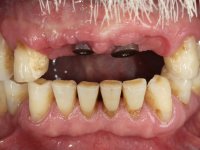

Paciente do sexo masculino, com 64 anos de idade, não fumador, recorreu á minha consulta após traumatismo do sector anterior. Os dentes 2.1 e 2.2 apresentavam extensas fraturas infra ósseas. Os dentes 1.2 e 1.1 apresentavam-se ferulizados com uma resina composta na zona inter-proximal. O dente 1.1 apresentava um tratamento endodôntico sofrível e um poste intra-radicular. O dente 1.2 estava vital e tinha uma extensa restauração da resina composta. Estando ferulizados, não foi possível avaliar o grau de mobilidade dentária de cada um dos dentes, mas o conjunto não tinha mobilidade. Após exame clínico e Imagiológico conclui-se que as raízes dos dentes 2.1 e 2.2 tinham extração indicada. O paciente estava reabilitado provisoriamente com uma prótese removível esquelética com 3 dentes. Apresentava algum comprometimento periodontal e os dentes mostravam as superfícies oclusais e incisais desgastadas. Higiene oral razoável.

Foi proposta a extração das raízes dos dentes 2.1 e 2.2. e colocação de 1 implante no local do dente 2.1 que suportaria uma ponte aparafusada com 2 elementos. O dente 2.1 sobre o implante e o 2.2 em extensão. Se em termos periodontais a zona do 1.2 e 1.1 continua-se a maturar sem problemas e se garantir-se um bom suporte sem mobilidade, seria proposto refazer o tratamento endodôntico do 1.1 e fazer o tratamento endodôntico no 1.2. Posteriormente e após colocação de postes intra-radiculares os dentes seriam reabilitados com uma ponte com 2 elementos. Após a colocação da ponte de2 elementos sobre o implante colocado no local do 2.1, o paciente sofre um novo traumatismo que compromete a viabilidade dos dentes 1.2 e 1.1. Nessa altura é proposta a colocação de um novo implante no local do dente 1.1 e confeção de uma ponte de 4 elementos com os dentes 1.1 e 2.1 sobre os implantes e os dentes 1.2 e 2.2 como pônticos em extensão.

6 meses após a colocação da ponte, o paciente sofre um novo traumatismo comprometendo a viabilidade dos dentes 1.2 e 1.1. Foi realizada uma prótese removível acrílica para reabilitar provisoriamente o paciente enquanto foram extraídos os dentes 1.2 e 1.1 e foi colocado o implante no local do dente 1.1. Passados 3 meses foi realizada uma impressão ao implante colocado no 1.1 e simultaneamente foi feito um arrasto da ponte dos dentes 2.1 e 2.2. Para esse efeito no implante 2.1 foi utilizado um parafuso de uma peça de transferência. Dessa forma conseguiu-se impressionar corretamente a arquitetura gengival do sector antero-superior. O objetivo era simultaneamente impressionar corretamente esta zona e aproveitar a estrutura metálica desta ponte para confecionar a nova ponte de 4 elementos. Foi colocado um parafuso de cicatrização no implante 2.1 e foram acrescentados os dentes 2.1 e 2.2 na prótese removível. Com perícia laboratorial foi criada uma nova infraestrutura metálica de 4 elementos assente nos implantes 1.1 e 2.1 e com os elementos pônticos suspensos 1.2 e 2.2. No implante 2.1 manteve-se a conexão interna ao implante no implante 1.1 optou-se por uma peça intermédia facilitando a inserção da infraestrutura. A nova infraestrutura foi verificada em boca. Como pode ter havido alguma alteração da arquitetura gengival com a remoção da ponte e colocação do parafuso de cicatrização no 2.1, foi feita uma chave de silicone para permitir uma impressão de arrasto da infraestrutura metálica. Uma nova gengiva artificial foi realizada no modelo de trabalho de acordo com esta impressão de arrasto. Foi colocada cerâmica de tonalidade coronária e gengival. A peça protética foi aparafusada lentamente em boca para permitir uma adaptação dos tecidos moles. Após o correto assentamento e verificação imagiológica a ponte foi definitivamente apertada em boca e os orifícios de acesso obturados. Independentemente dos infortúnios que o paciente teve, pude ter a satisfação de o ver contente com esta reabilitação.